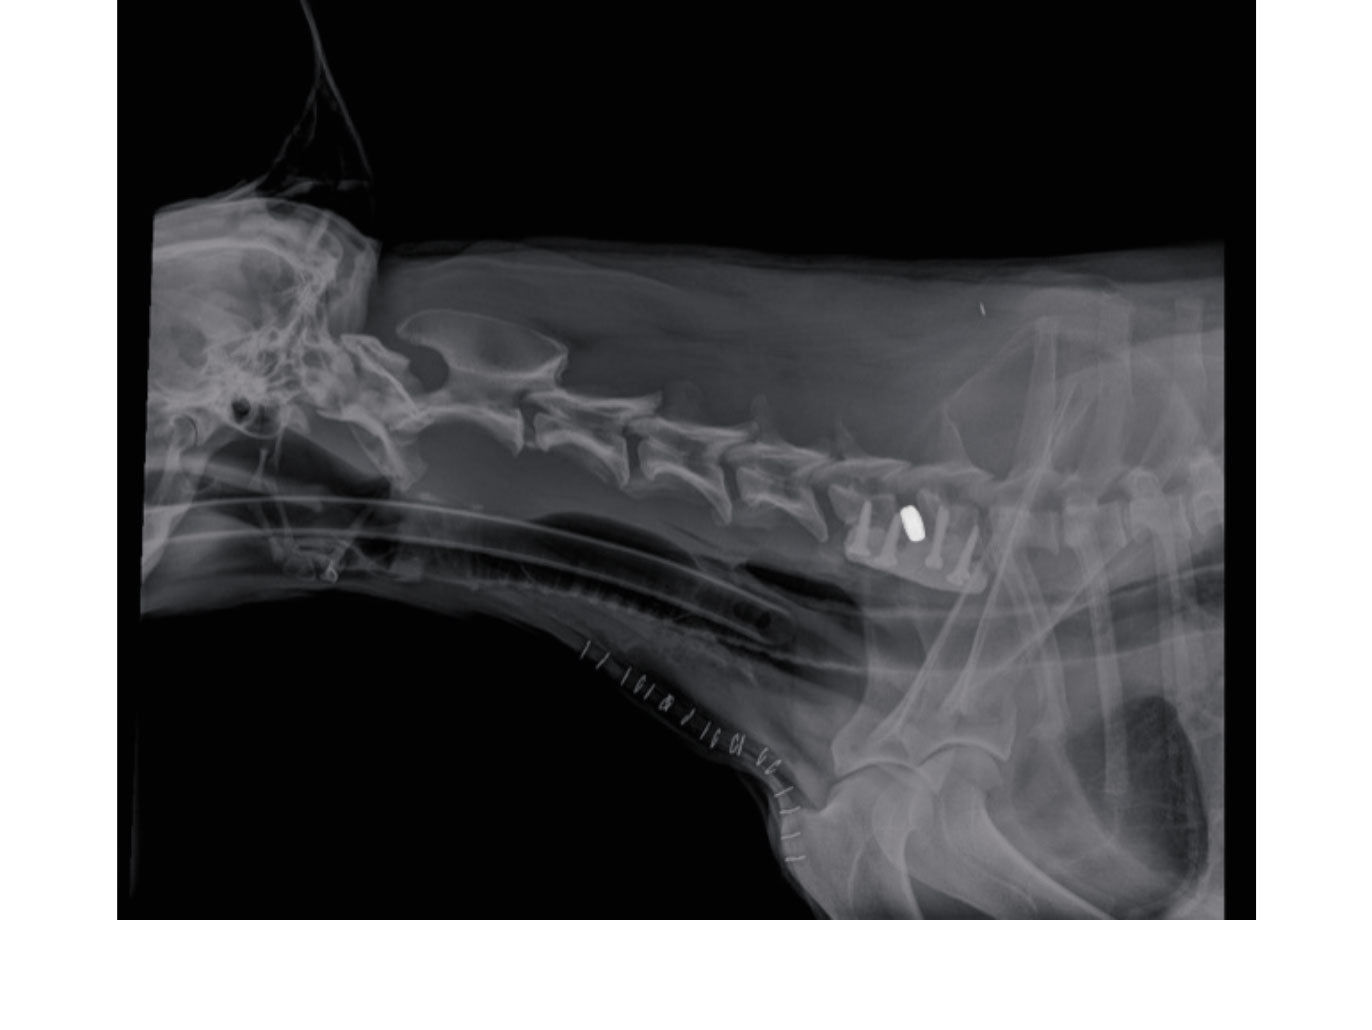

• Ventral cervical screw placement for spinal stabilisation

Ventral stabilisation techniques of the subaxial cervical spine are taught in our advanced courses. The placement of screws in these techniques is extremely intricate – learning the importance and in what way to use drill stops is focal.

// User Cases

Highlighting the cases of these products in real-life situations is vital to demonstrating their success. Below are cases studies of long-term follow up surgeries.